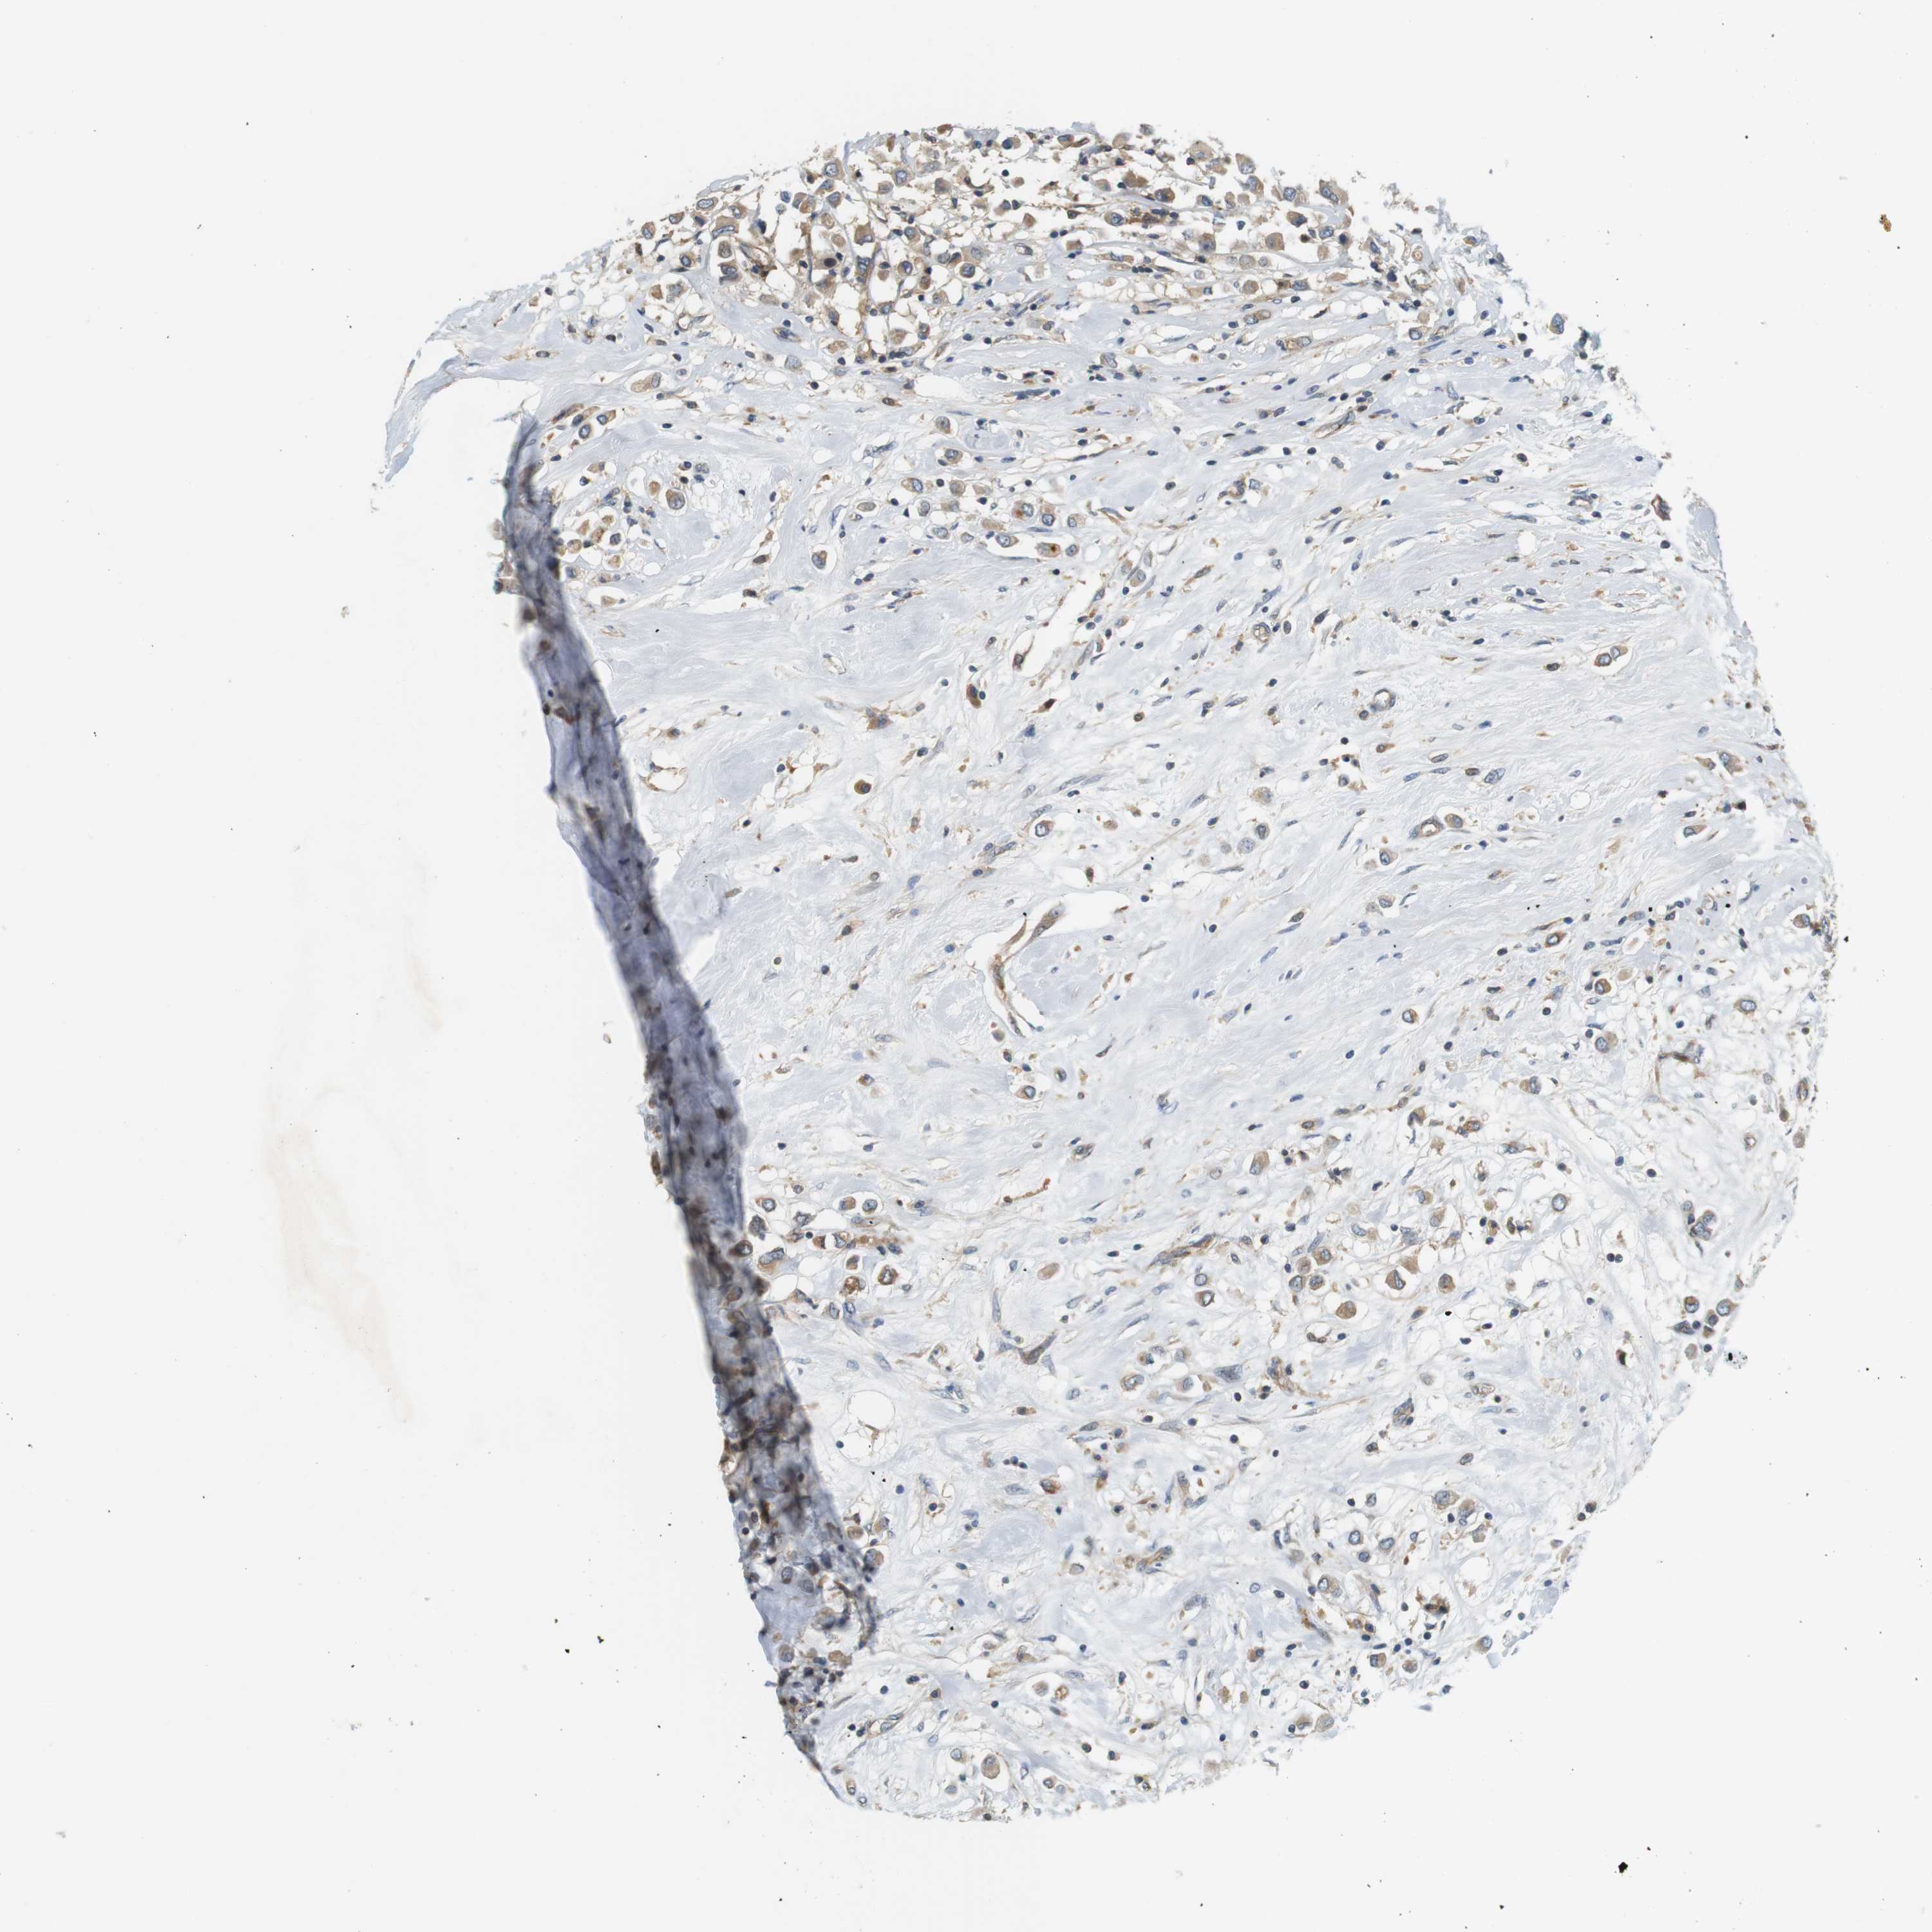

CANCER BREAST CANCER Show tissue menu

BRCA TCGA BRCA VALIDATION PROTEIN EXPRESSION